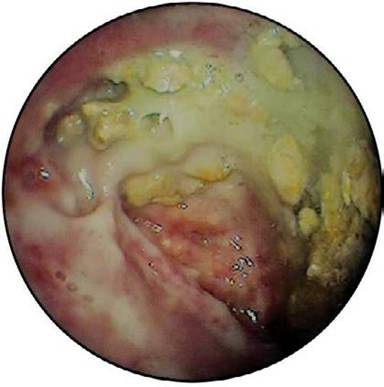

A seventy two-years old male presented with fever, abdominal discomfort and vomiting six weeks after an episode of gall stone acute pancreatitis. An i.v. contrast abdominal Ct scan revealed a cystic collection 6x7 cm with air level at the tail of pancreas bulging towards stomach. Lab exams revealed only leukocytosis. On gastroscopy a small fistulous opening was found at the posterior wall of upper stomach corpus. A pus like discharge from the opening was noted (Figure 1). Further, the fistulous opening was step-wise dilated so that the instrument tip carefully entered the cavity (Figure 2). The cavity was full of debris, semi-solid necrotic material and a greenish liquid. Culture sample and cytology were both negative. The debris was aspirated through the scope meticulously. Further, the cavity was thoroughly irrigated with sterile normal saline and a nasobiliary catheter was left inside to secure a continuous irrigation along with drainage. The patient was kept on nil by mouth, i.v. broad spectrum antibiotics and gradually recovered uneventfully. White blood cells returned to normal and an i.v. contrast CT scan two months later depicted no fluid collections.

Figure 2. Walled-off pancreatic necrosis interior. |